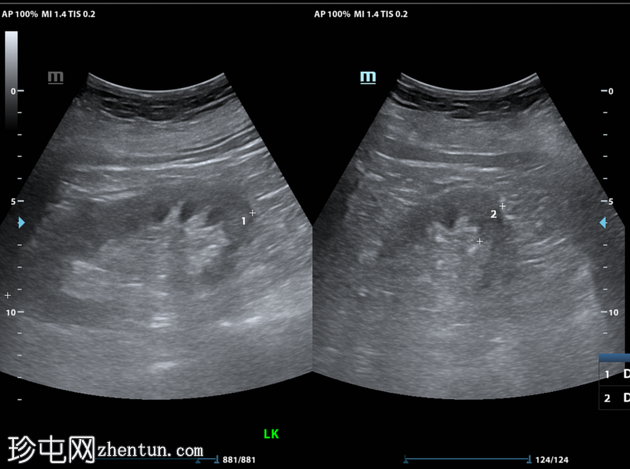

超声检查

2.png

肝胆系统

3.png

肝脏第6和第7段可见多个高回声气体腔,遮挡肝脏后部

肝脏其他部位形态及回声纹理正常

胆总管扩张,无结石,肝内胆管未见扩张

其他方面正常无游离液体